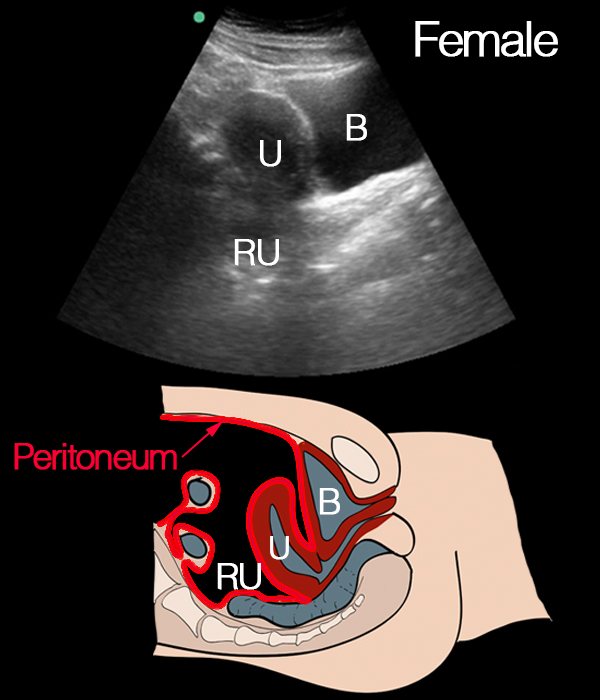

Normal longitudinal view of male pelvis: This longitudinal view shows the normal anatomy of the male pelvis. The bladder (B) is visible, along with the rectum (RU). This image provides a reference for identifying these structures in the male pelvis in the longitudinal plane.